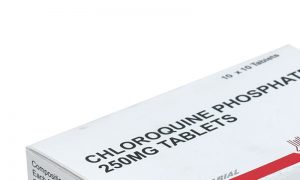

وزرا کی مخالفت کام نہ آئی، کلوروکوئن برآمدکرنیکی اجازت مل گئی

برآمد کرنے کی سخت مخالفت وفاقی وزرا اسد عمر، شیخ رشید احمد، شفقت محمود اور شیریں مزاری نے کی۔